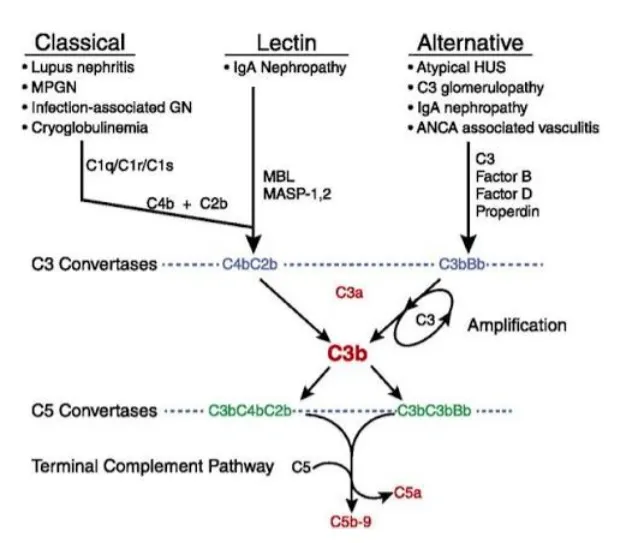

A GNC3 é resultado de ativação não controlada da via alternativa do complemento. Mutação de proteínas reguladoras (C3, fator B, fator H) ou presença de autoanticorpos como o fator nefrítico do C3 levam a deposição glomerular de C3.

O sequenciamento genético revelou uma mutação no éxon 19 do gene C3, presente também no filho e no irmão da paciente. Após vacinação adequada, foi iniciado lisinopril e eculizumabe, com melhora da creatinina (0,9 mg/dL) e estabilização da proteinúria.

Mais tarde, foi incluída em estudo com iptacopan, um inibidor seletivo da via alternativa do

complemento.

A GNC3 é uma doença de descoberta recente, muitas vezes confundida com GN pós-infecciosa. Reconhecer o padrão de deposição de C3 e solicitar investigação genética são passos cruciais especialmente agora, com terapias direcionadas ao complemento disponíveis.